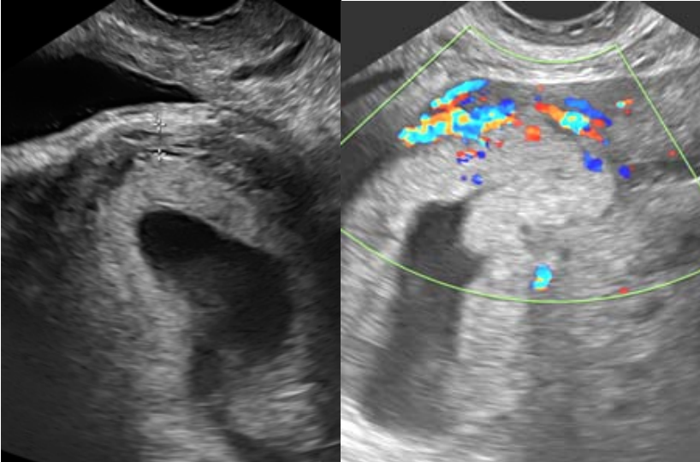

Paciente, 31 anos, tercigesta (duas cesarianas anteriores), na 7ª semana de gravidez com queixa de sangramento genital há 15 dias, com piora há 24 horas. Ao exame, encontrava-se com estado geral bom, hipocorada (+/4+), acianótica, consciente e orientada. Pressão arterial de 120 x 80 mmHg. Frequência cardíaca de 88 bpm. Abdome plano depressível e indolor, sem massas palpáveis e ausência de sinais de irritação peritoneal. Submetida a exame ultrassonográfico transvaginal, com a imagem abaixo revelando saco gestacional dentro de cavidade uterina, de contorno regular, em topografia de istmocele.

Assinale a alternativa a qual sugere a principal hipótese diagnóstica.